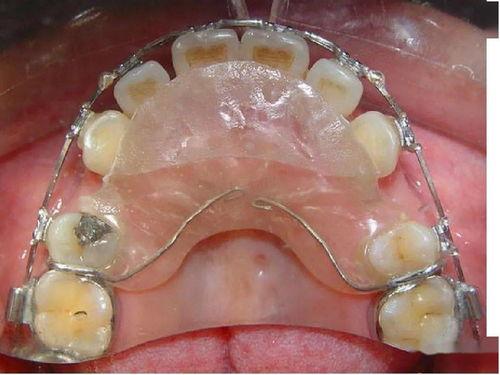

隨著正畸技術(shù)的不斷發(fā)展,如今有多種方法可以應(yīng)對(duì)嚴(yán)重畸形的牙齒。例如,傳統(tǒng)的金屬托槽矯正、陶瓷托槽矯正、自鎖托槽矯正,以及近年來越來越受歡迎的隱形矯正等。

嚴(yán)重畸形的牙齒能否矯正